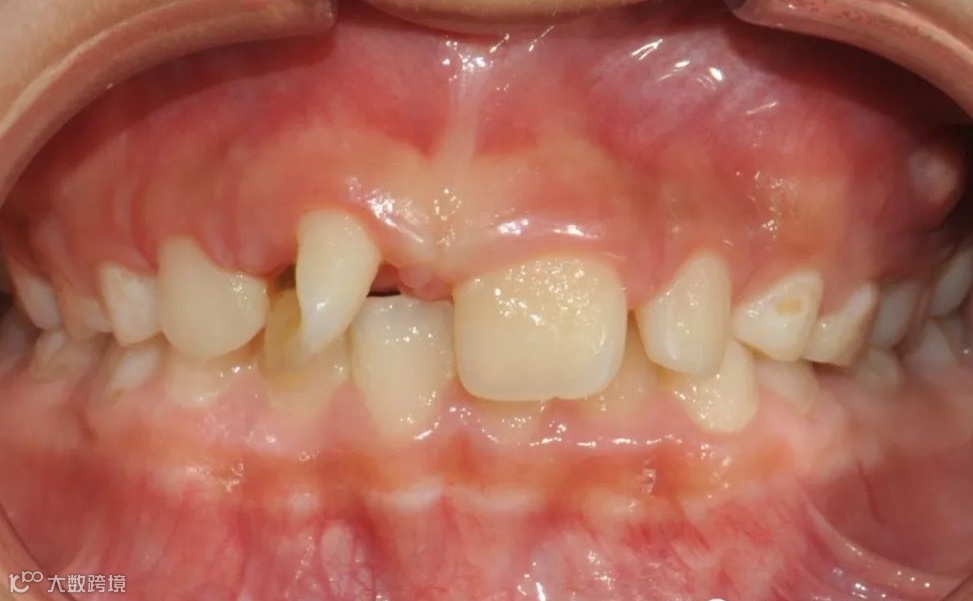

替牙期牙性反𬌗治疗前

替牙期牙性反𬌗治疗后